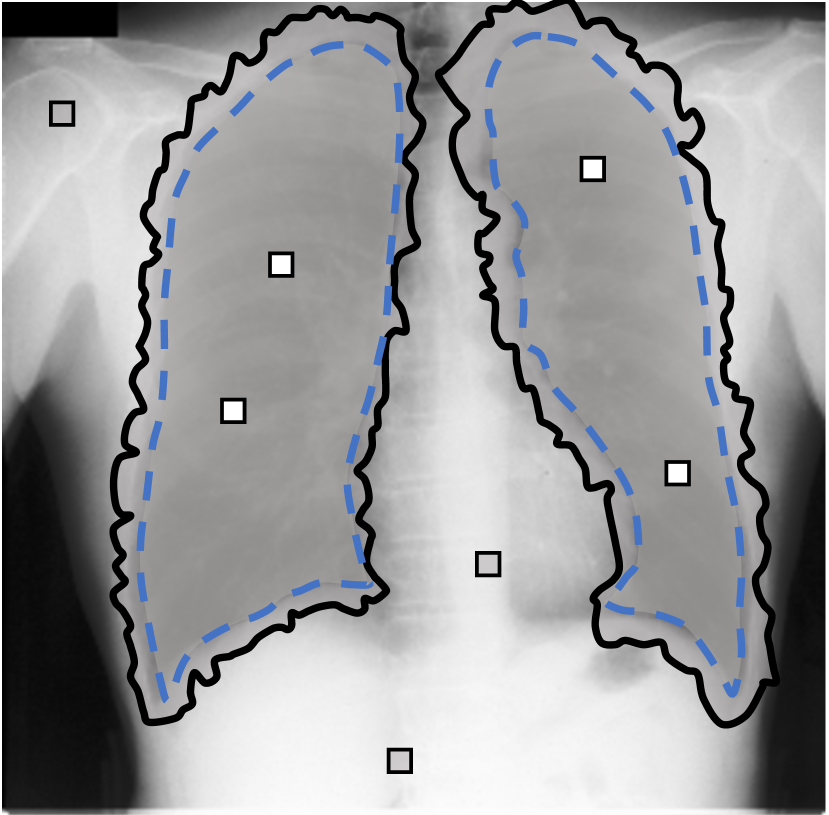

For each of these three datasets, we use three noise settings, denoted by , and . and are two settings synthesized by our Markov process with (expansion) and (shrinkage), respectively. Figure 4 shows examples of our synthesized label noise. We also include the mix of random dilation and erosion noise used by previous work (Zhu et al., 2019; Zhang et al., 2020b; a). This is achieved by randomly dilate or erode a mask with a number of pixels. Note that our Markov label noise can theoretically include this type of noise by setting . Detailed parameters for these settings are provided in the Appendix.

Real-world label noise. To evaluate with real-world label noise is challenging. We are not aware of any public medical image segmentation dataset that has both true labels and noisy labels from human annotators. Therefore, we use a multi-annotator dataset, LIDC-IDRI dataset (Armato III et al., 2015; Armato et al., 2011; Clark et al., 2013), and the coarse segmentation in a vision dataset, Cityscapes (Cordts et al., 2016). The LIDC-IDRI dataset consists of 1018 3D thorax CT scans where four radiologists have annotated multiple lung nodules in each scan. The dataset was annotated by 12 radiologists, and it is not possible to match an annotation to an expert. We use the majority voting as the true labels and the union of four annotations as noisy labels. We process and split the data exactly the same way as Kohl et al. (2018). Cityscapes dataset contains 5000 finely annotated images along with a coarse segmentation by human annotators that we use as the “noisy label”. We only focus on the ‘car’ class because (1) cars are popular objects and are frequently included in images; (2) the coarse annotation of cars is very similar to noisy annotation in medical imaging – they are reasonable distortions of the clean label without changing the topology. See Figure 4(c) for an example. The detailed settings of LIDC-IDRI and Cityscapes can be found in Appendix A.2.1.